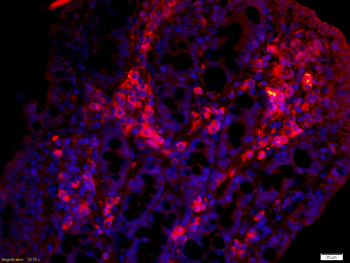

50 μl, 100 μl, 200 μlTIG2 Rabbit Polyclonal Antibody [orb11481]

IF, IHC-Fr, IHC-P

Human, Mouse, Rabbit

Human, Mouse, Rabbit, Rat

Rabbit

Polyclonal

Unconjugated

50 μl, 100 μl, 200 μlAnti-Aurora A/AURKA Antibody [orb1290027]